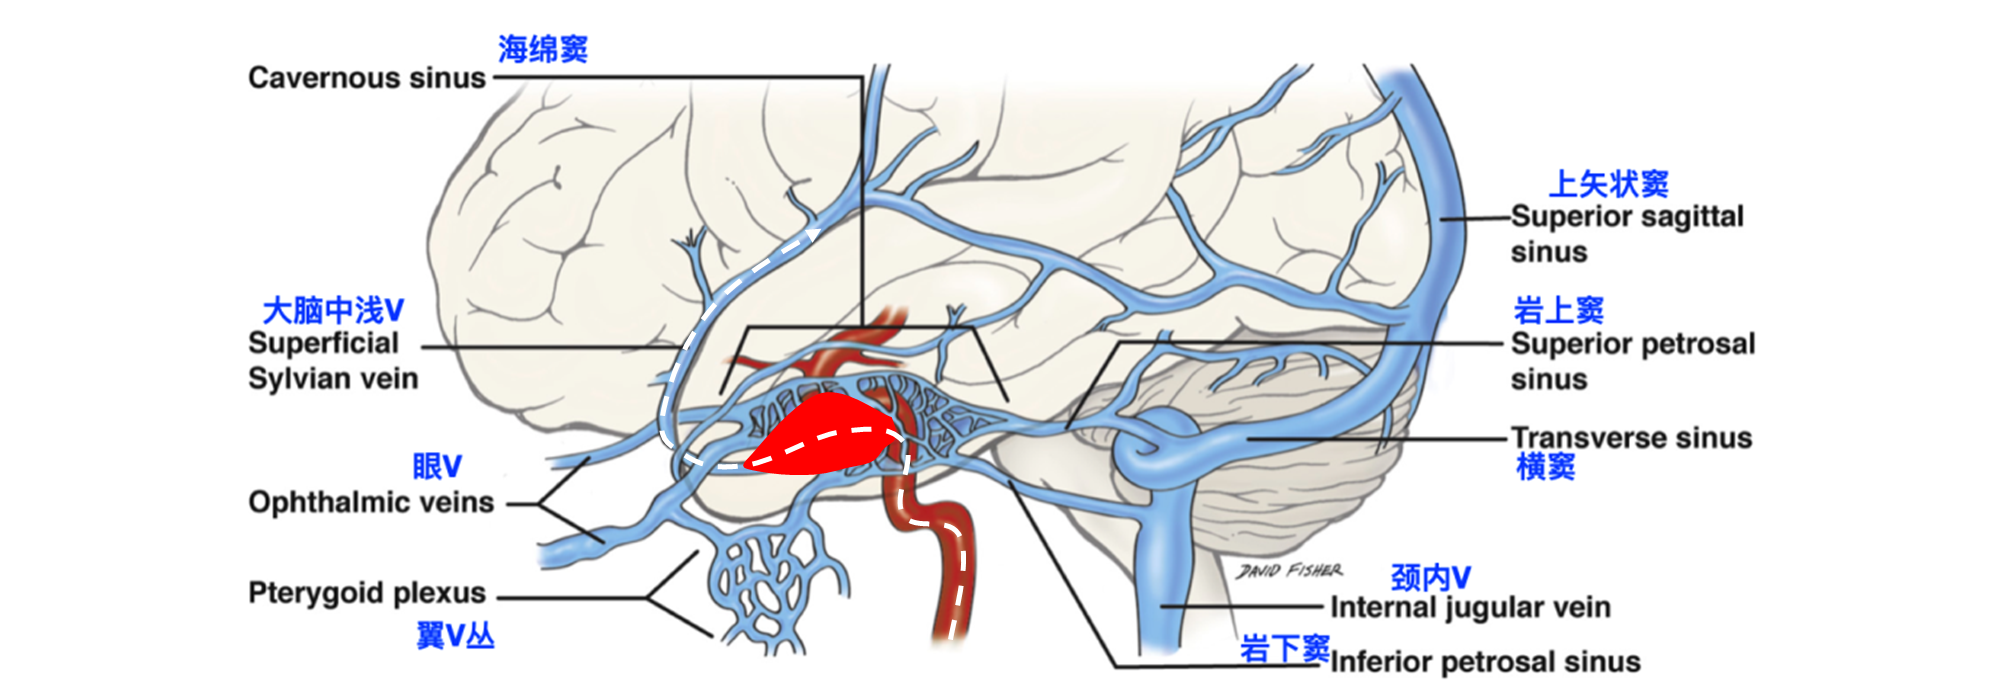

2. 左侧颈内C4段动脉瘤破裂致颈内动脉海绵窦瘘(Barrow A型)

精确诊断:左侧颈内C4段动脉瘤破裂至大脑中浅静脉致左侧基底节区及左侧额颞叶静脉性梗死并出血转化。

颈内动脉海绵窦瘘( CCF)的典型临床表现为搏动性突眼、球结膜充血、血管性杂音、耳鸣是CCF最常见的临床症状。颈内动脉及其脑膜支穿过海绵窦,一旦这些动脉破裂,动脉血便直接流入静脉窦内,使窦内压升高,逆流入眼上静脉,回流受限,表现出搏动性突眼、眼肌麻痹、球结膜充血以及与动脉搏动一致的血管性杂音等症状。海绵窦段动脉瘤破裂也是导致CCF的其中原因之一,但是其导致出血转化比较少见。本病例的难点在于诊断,通过大管+微导管造影才最终确诊。而最终的诊断和初步诊断差别悬殊。如果按初步诊断和治疗方案,可能造成不良后果,而单栓+穿刺的配合使得病人取得良好预后。因此要重视脑血管病责任病灶的诊断,不可一叶障目而不识神秀岱宗。